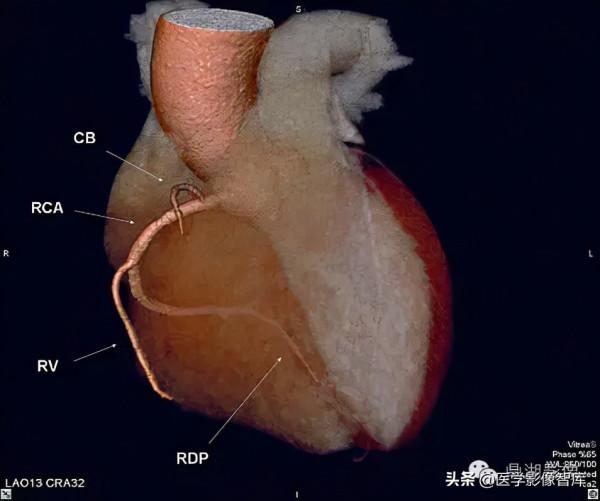

Maximum Intensity Projection (MIP)右圓錐支(CB)